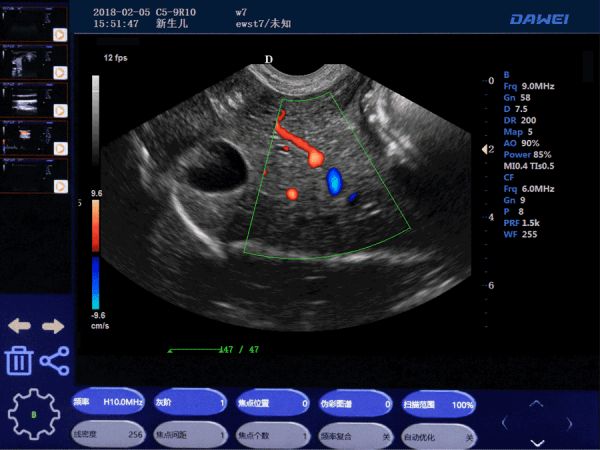

● 实时空间复合成像

● 梯形成像

● 组织谐波成像技术(THI)

● 实时三维成像(4D)